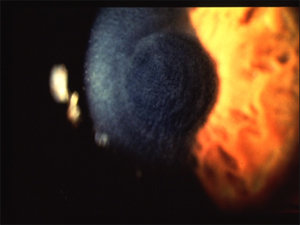

上皮迷入 Epithelial ingrowth

上皮細胞はフラップにおける傷を通してあるいは実質底の洗浄中に洗い流されることによって、実質底への通り道を作る。上皮迷入は、術後数日から数週間で顕著となり、そして傷がフラップへの新しい損傷にならないかぎり、回復時の遅い時期には起こらない。いったんフラップの下に入るや否や、上皮細胞は成長するか、そのまま安定していることもある。

境界面の上皮細胞はさまざまな外見をしており、その規模によって1から3まで段階(グレード)付けられる。グレード1の上皮細胞はほぼ透明で発見するのが困難である。普通これらはフラップの縁付近にあり、境界線をきれいになぞっている。グレード1の上皮細胞は非進行性であり、外科的処置は必要としない。グレード2の上皮細胞は少しもや状にかすみ、はっきりした境界線無しに細胞の一群の中に見ることができる。グレード2の細胞は進行性なので治療が必要である。グレード3の上皮細胞は、内部成長と溶けた実質のもや状で不透明な部分によって特徴付けられる。これらは緊急の外科的処置が必要となる。

Img4

スライド#4 グレード3の上皮細胞

上皮細胞内部成長の治療としては、フラップを持ち上げて境界面から上皮細胞をぬぐい去ることである。上皮細胞は、あらゆる残余細胞をも取り除くために角膜実質の洗浄を繰り返し行うことによって発生する、活動的な細胞(wick cells)と一緒に簡単に取り除かれてしまうのが一般的である。術後フラップを持ち上げるのが早ければ早いほど、外傷がフラップに残る事も少なく、又細胞も容易に取り除くことができる。

あらゆる上皮細胞は進行に関して絶えず監視する必要がある。上皮内部細胞は週に一回チェックをし、安定性が確立されるまで注意深く記録するべきである。写真記録は便利であるがもしそれが利用できない場合、大きさや位置を示した図が細胞が進行しているかどうかを決定付ける助けとなる。視軸上の上皮細胞は、未矯正の視力の低下やあるいは最高矯正視力の低下に帰着し、治療が必要となる。乱視や融解したフラップもまた上皮内部成長によって引き起こり、その患者は細胞切除のために外科医に再度紹介すべきであることを示唆するのである。